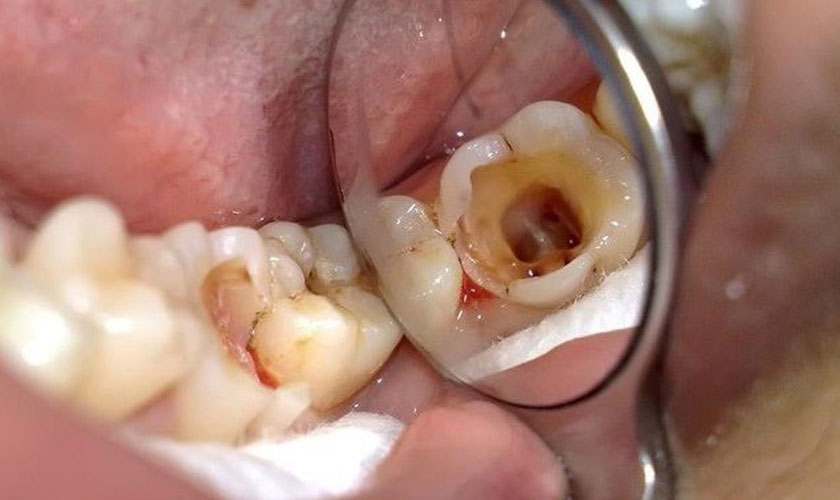

🦷🔥 Viêm tủy răng xảy ra khi vi khuẩn xâm nhập vào buồng tủy (mạch máu – thần kinh), gây đau dữ dội và biến chứng nguy hiểm nếu trì hoãn.

Mở buồng tủy – làm sạch bằng trâm máy